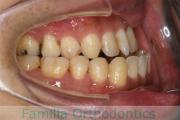

歯並びを綺麗にしたいということで来院されました。叢生(でこぼこ、凹凸、ガタガタ)と上下顎前突のため、上下左右から小臼歯を抜歯の上で、歯科矯正用アンカースクリューを併用したマルチブラケット法を行いました。約2年半、30回の通院が必要でした。

上下とも叢生がありますので、後戻りのリスクがあります。